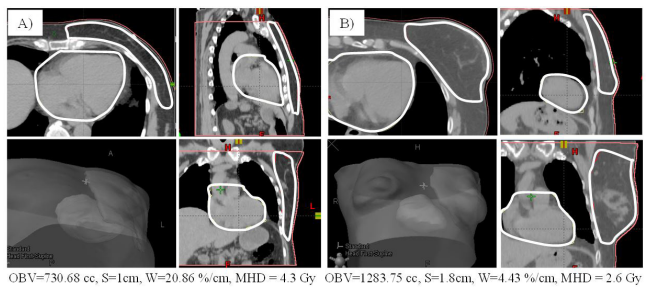

| Figure 3: geometrical configuration of anatomical structures for two different patients A) and B). Omolateral breast and heart boundaries are shown in white for planar images and in gray for 3D representations. Predicted MHD was 4.6 and 2.7 Gy for patient A) and B), respectively |

Although preliminary, our results help us to better clarify the connection between MHD and the geometric layout involved in the radiotherapy treatment of the left breast in a context of a homogeneous setting of both technique and dose prescriptions. Our geometrical analysis is simple, but not trivial. In particular, the wrapping parameter, W, proved to grasp some aspects of the spatial arrangement of radiotherapy volumes relevant for their impact on heart dosimetry. Nevertheless, W, as well as the other parameters in the model can be easily calculated using standard tools integrated in all commercial TPSs. In order to visualize the descriptive power of our parameters in comparing different patients, an example is pictured in Figure 3. It is apparent from the figure the ability of S and W to describe a more challenging geometry for patient A) having the heart closer to the irradiated breast (with a smaller S) and for a much larger extent of its surface (larger W). This can explain why MHD is lower for patient B), in spite of the bigger target volume.